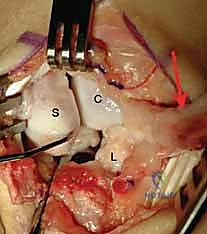

Here, the exposure highlights the ulnar-based dorsal capsular flap. The DIC parallels the transverse limb of the flap. The scaphoid, lunate, and triquetrum are clearly visualized beneath the reflected tissue.

This ulnar-based flap is carefully elevated off the underlying carpus, preserving its vascularity and structural integrity. It is imperative that this flap is at least 1 cm wide and of sufficient length to reach the distal pole of the scaphoid later in the procedure.

Once the capsule is reflected, the devastating pathology of the SLIL disruption is immediately apparent. We systematically inspect the radiocarpal and midcarpal articular surfaces to confirm the absence of advanced chondromalacia.

Observe the classic DISI deformity. The scaphoid is severely flexed, and the lunate is extended. The complete disruption of the SLIL is evident, leaving a yawning gap between the two carpal bones.